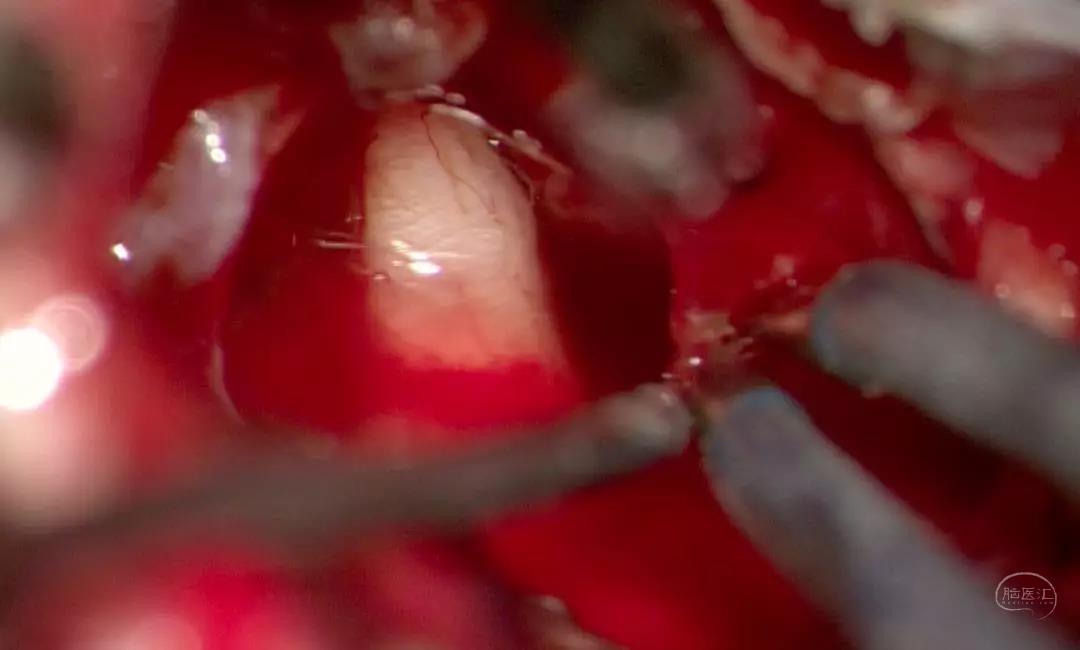

术中

时长:3h

肿瘤质地:囊实性

磨开内听道后壁 显露内听道内肿瘤

边冲水 边沿包膜分离肿瘤

封堵内听道 预防脑脊液漏

肿瘤切除后显露神经

磨开内听道后壁 显露内听道内肿瘤

边冲水 边沿包膜分离肿瘤

肿瘤切除后显露神经